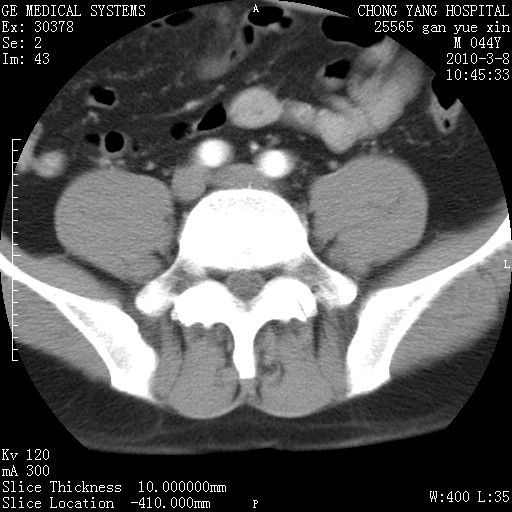

标题: CT24940:主动脉增强,典型病例。 [打印本页]

标题: CT24940:主动脉增强,典型病例。

夹层动脉瘤。

动脉夹层

夹层动脉瘤,典型

主动脉夹层。

动脉夹层的分型:

⒈debakey分型:根据主动脉夹层累及部位,分为三型:ⅰ型:原发破口位于升主动脉或主动脉弓部,夹层累及升主动脉、主动脉弓部、胸主动脉、腹主动脉大部或全部,少数可累及髂动脉。ⅱ型:原发破口位于升主动脉,夹层累及升主动脉,少数可累及部分主动脉弓。ⅲ型:原发破口位于左锁骨下动脉开口远端,根据夹层累及范围又分为ⅲa,ⅲb。ⅲa型:夹层累及胸主动脉。ⅲb型:夹层累及升主动脉、腹主动脉大部或全部。少数可累及髂动脉。

⒉stanford分型:a型:夹层累及升主动脉,无论远端范围如何。b型:夹层累及左锁骨下动脉开口以远的降主动脉。

夹层动脉瘤,少量胸水

夹层动脉瘤;左侧少量胸腔积液。

典型主动脉夹层。